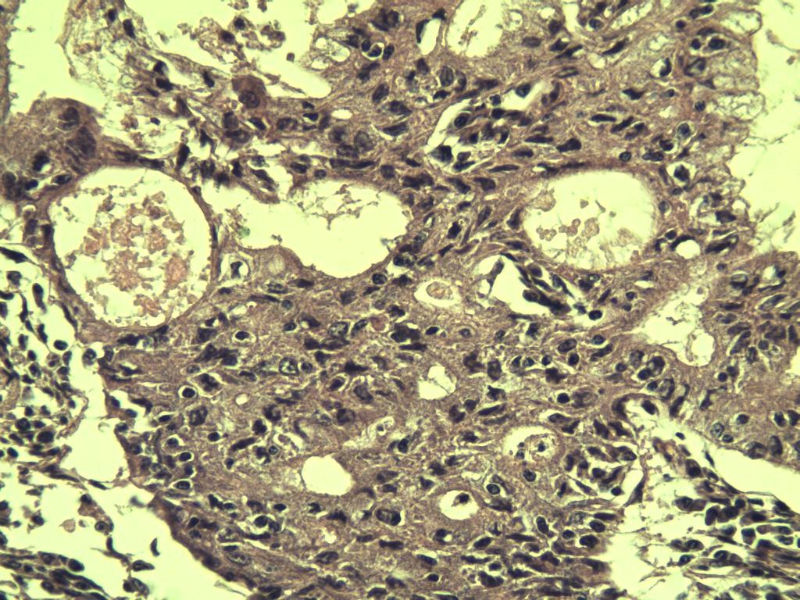

女,57岁,全切子宫一个,宫体体积 9 × 8 × 7 cm3,肌壁厚 2.5 cm,内膜菲薄,部分区域增厚达 0.4 cm(约3*2.5cm区域)。 请问各位老师  这个可以诊断子宫内膜癌了吧?      深肌层没有看到浸润。

患者因"发现下腹部包块1月多"入院  宫体体积 9 × 8 × 7 cm3,肌壁厚 2.5 cm,内膜菲薄,部分区域厚 0.4 cm(约3*2.5cm)。宫颈结构不清,长约 2.5 cm,表面欠光滑。临床诊断宫颈宫腔积液.

宫内膜样腺癌

筛状、迷路样结构

间质消失或者纤维性间质

子宫内膜样腺癌

高分化子宫内膜样癌。浸润浅肌层(深度<1/3肌层)。根据FIGO2009分期,子宫内膜癌局限于内膜层和<1/2肌层,都属于IA期。二者处理不再区别对待。